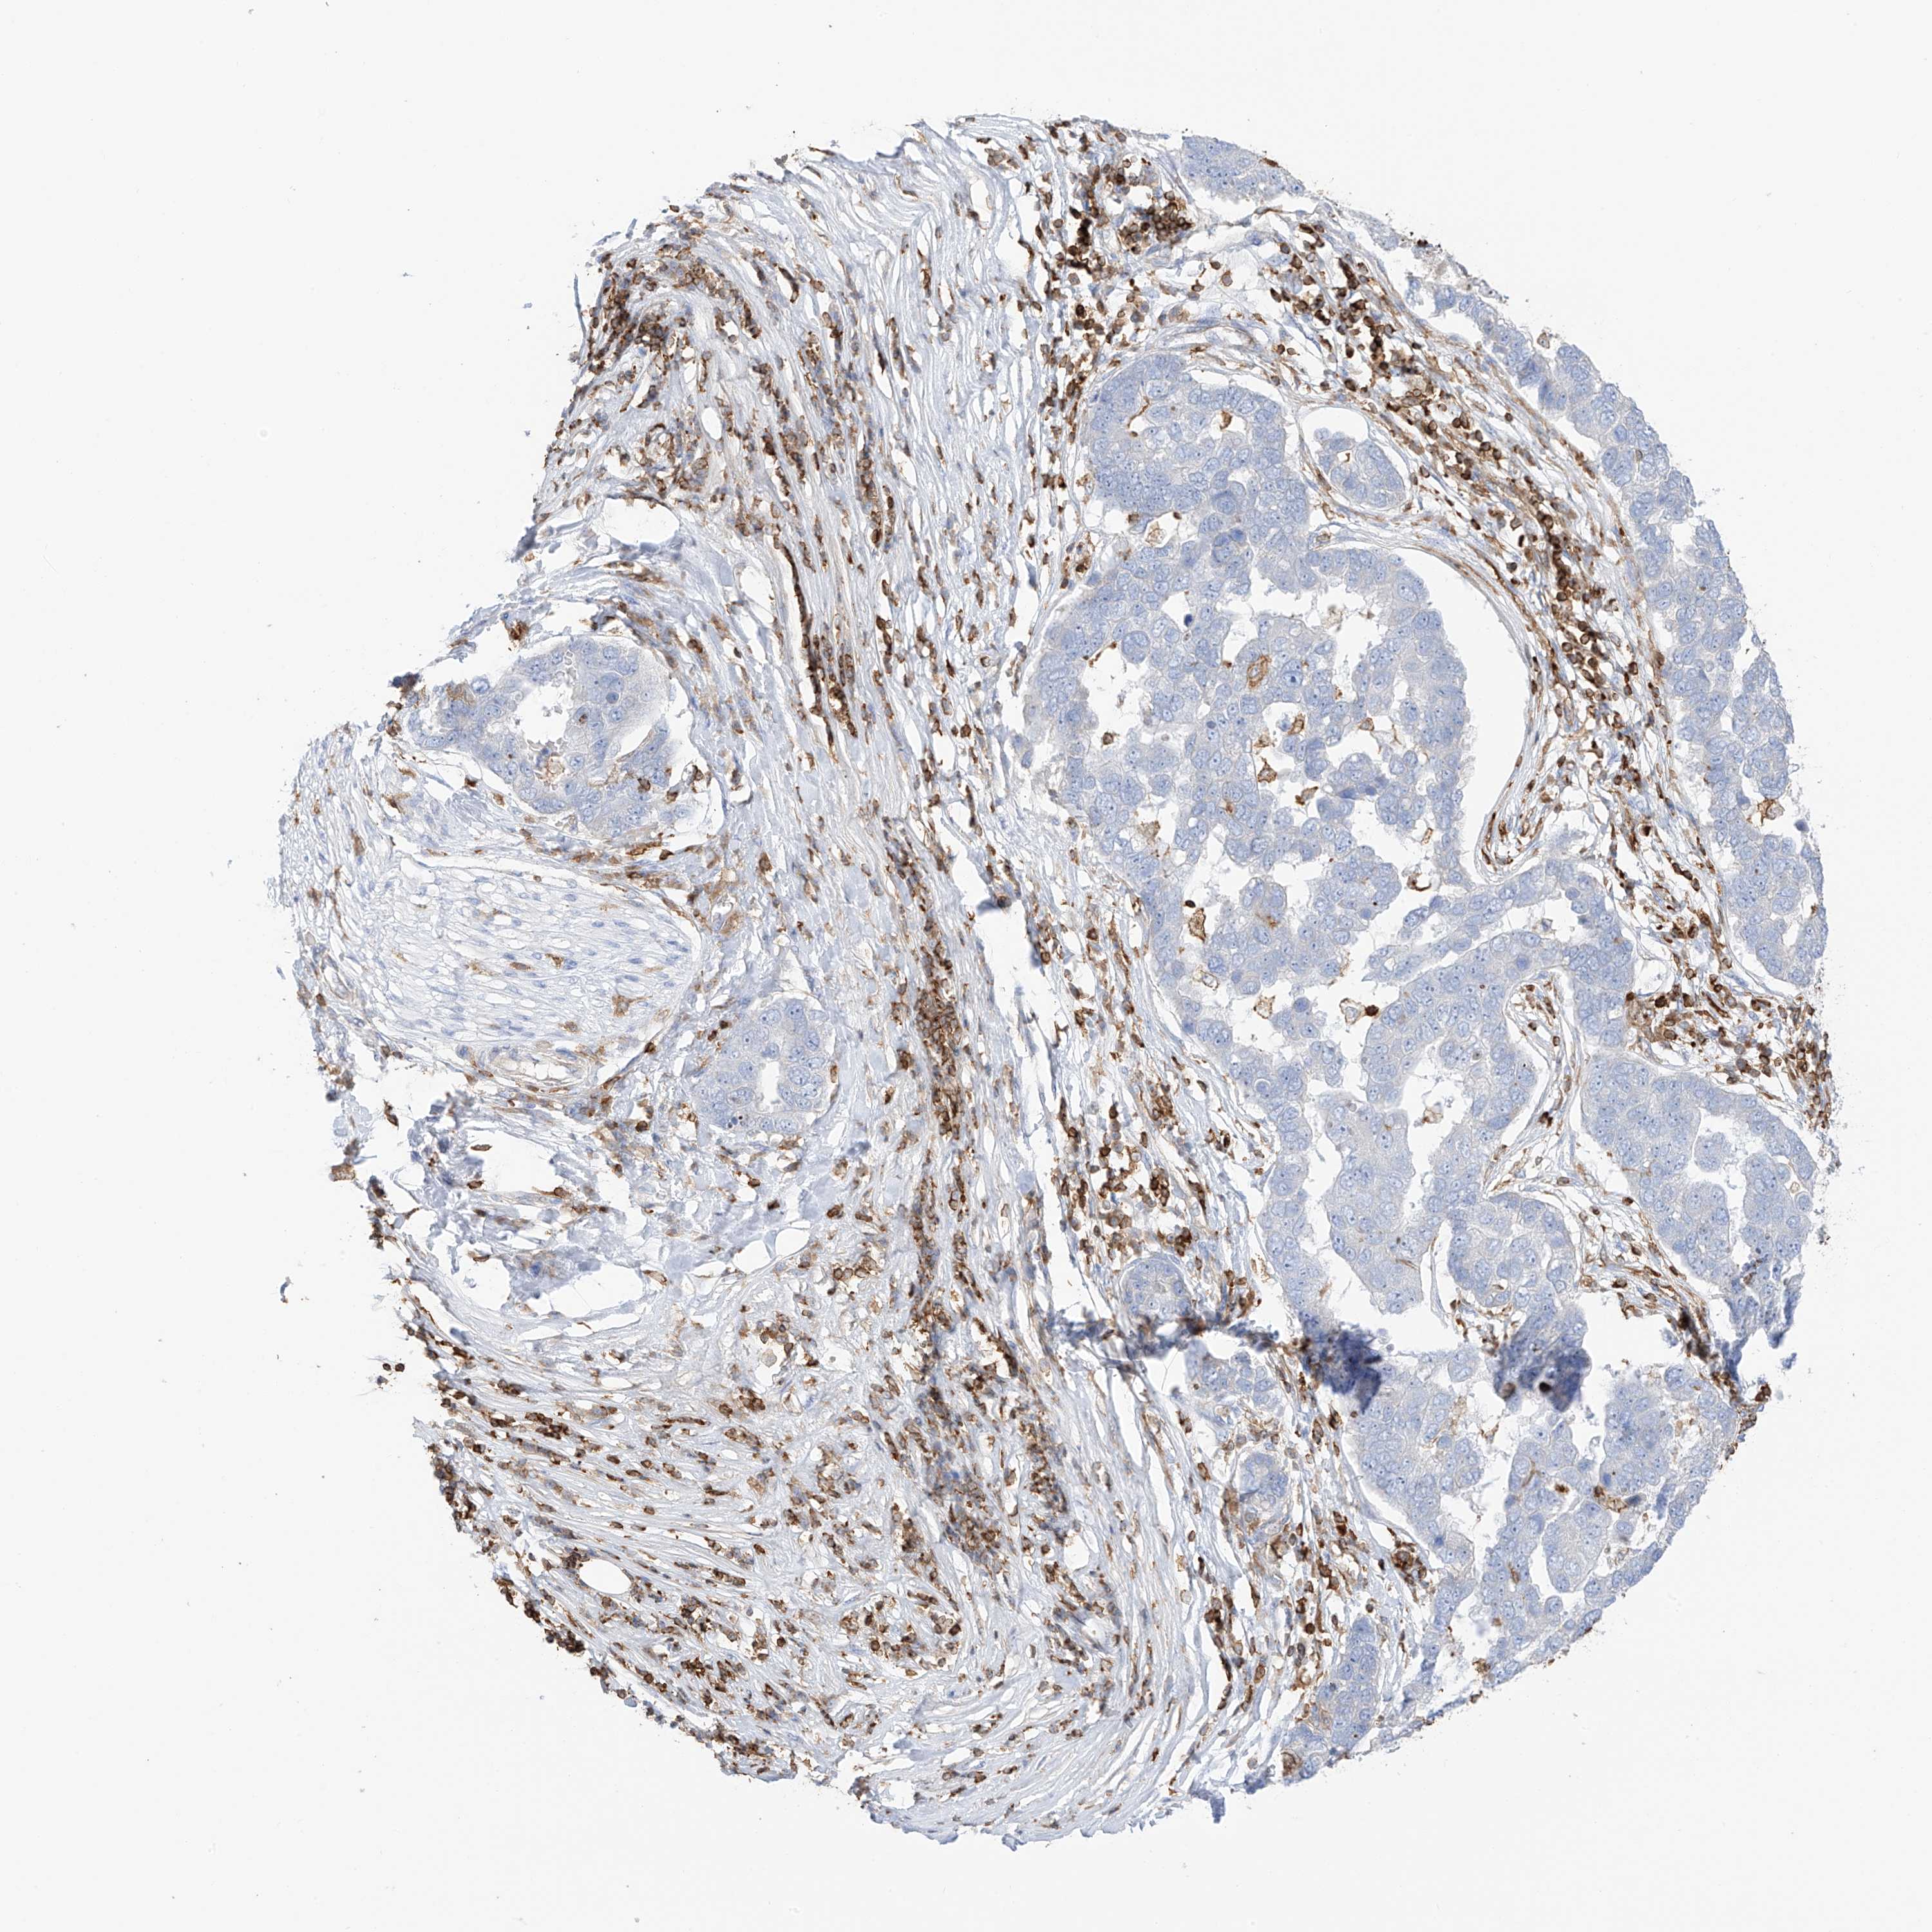

PANCREATIC CANCER - Protein expressioni

A mouse-over function shows sample information and annotation data. Click on an image to view it in a full screen mode. Samples can be filtered based on level of antibody staining by selecting one or several of the following categories: high, medium, low and not detected. The assay and annotation is described here.

Note that samples used for immunohistochemistry by the Human Protein Atlas do not correspond to samples in the TCGA dataset.

Antibody stainingi

Antibody staining in the annotated cell types in the current human tissue is reported as not detected, low, medium, or high, based on conventional immunohistochemistry profiling in selected tissues. This score is based on the combination of the staining intensity and fraction of stained cells.

Each image is clickable and will lead to virtual microscopy that enables deeper exploration of all samples and also displays staining intensity scores, fraction scores and subcellular localization as well as patient and tissue information for each sample.

Antibody HPA035346

Antibody HPA061395

Staining

High

Medium

Low

Not detected

Intensity

Strong

Moderate

Weak

Negative

Quantity

>75%

75%-25%

<25%

None

Location

Nuclear

Cytoplasmic/membranous

Cytoplasmic/membranous,nuclear

Adenocarcinoma, NOS